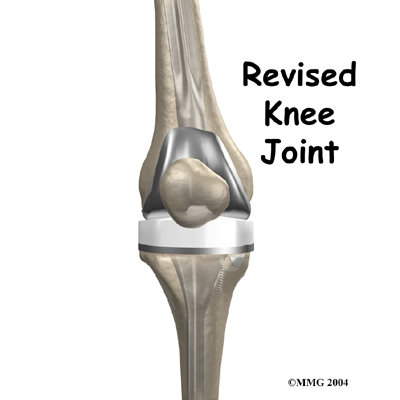

Revision Arthroplasty of the Knee

Over the past 30 years, artificial knee replacement surgery has become increasingly common. Millions of people have gotten a new knee joint. The first time a joint is replaced with an artificial joint the operation is called a primary joint replacement. As people live longer and more people receive artificial joints, some of those joints begin to wear out and fail. When an artificial knee joint fails, a second operation is required to replace the failing joint. This procedure is called a ...